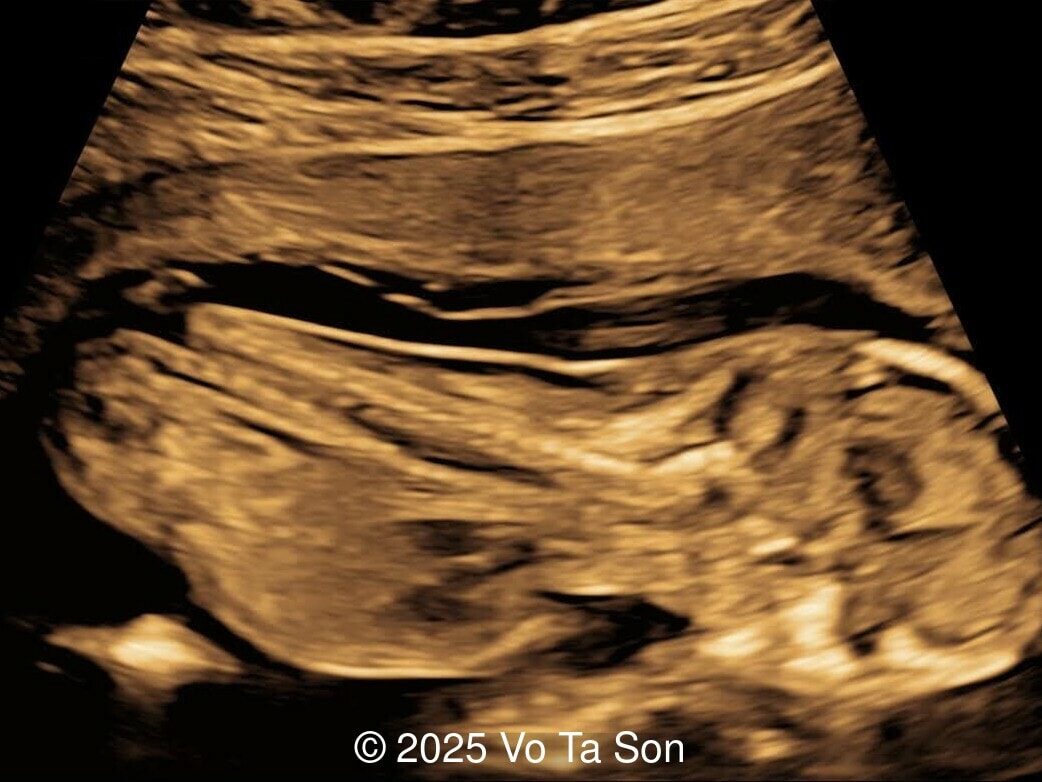

A woman underwent routine prenatal screening at 13 weeks. The non-invasive prenatal test (NIPT) showed low risk for common aneuploidies including trisomy 21, 18, and 13. However, first-trimester anomaly scan revealed multiple fetal anomalies.

Please describe the abnormalities and provide a syndromic diagnosis that best fits the presentation.